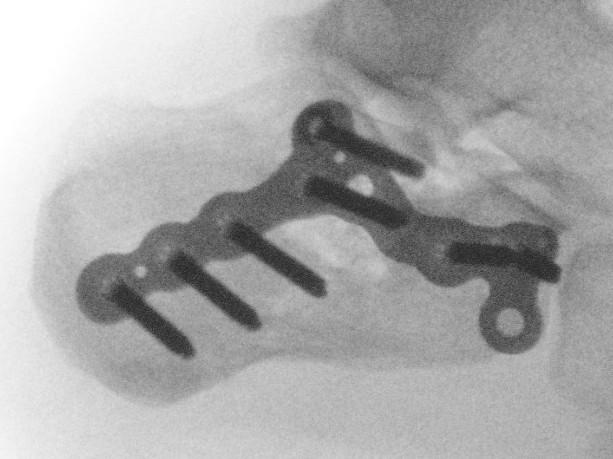

Percutaneous Fixation

Technique

Needs to be performed 3 - 5 days after injury while fracture fragments mobile

- 287 displaced intra-articular fractures

- MUA / Gissane spike percutanous reduction / K wire fixation

- 72% good or excellent results

- 1.7% deep infection, 7% superficial infection